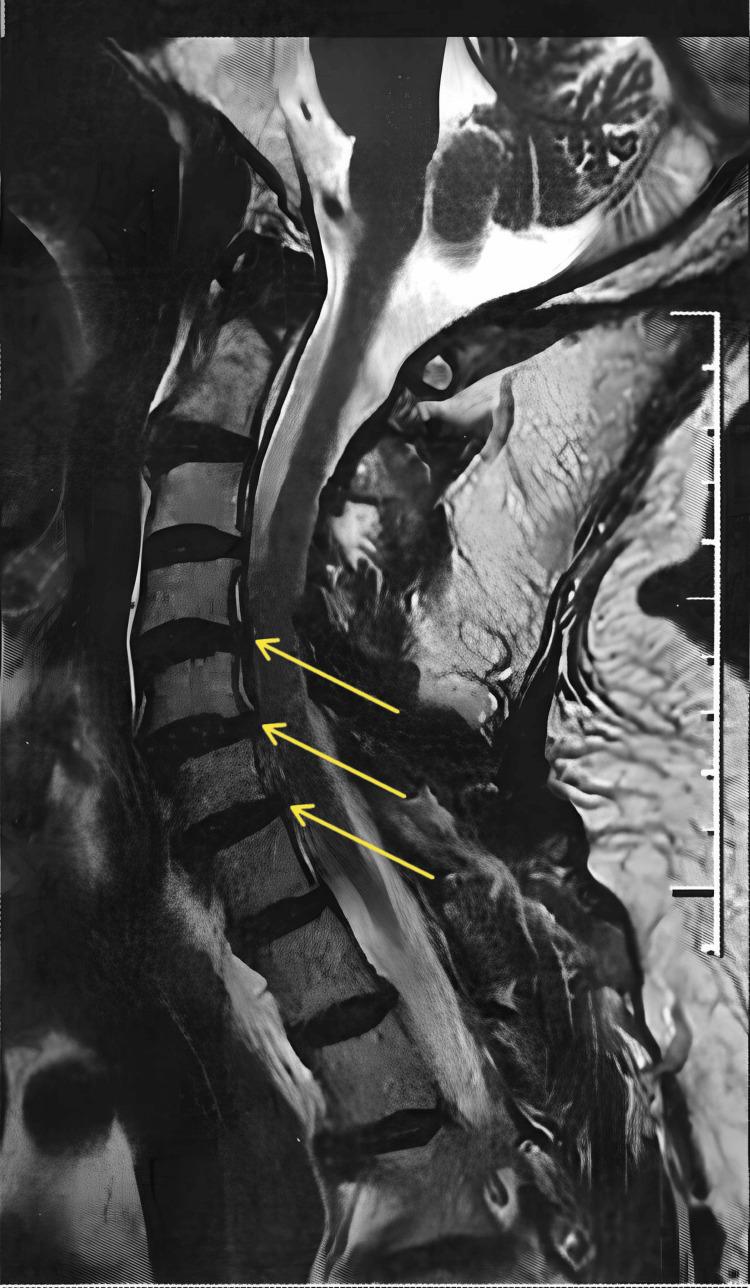

Spondyloarthritis (SA) is a chronic inflammatory disease that predominantly affects the spinal column. SA-related pain can be intense, persistent, and disabling. Studies with cannabis have been conducted involving patients with refractory epilepsy, multiple sclerosis, Parkinson's disease, sleep disorders, and chronic pain. Cannabidiol is the major non-psychotropic component of cannabis, has anti-inflammatory and analgesic properties, and exerts anxiolytic and mood-stabilizing effects. This paper reports a case of a 72-year-old male with SA, with mild stenoses of the spinal canal at C4-C5 and C5-C6 and stenoses of the left neural foramina at C3-C4, C4-C5, C5-C6, and C6-C7. The use of cannabidiol in our patient achieved satisfactory results in the control of pain related to cervical spondyloarthritis.

脊柱关节炎(SA)是一种主要影响脊柱的慢性炎症性疾病。SA相关的疼痛可能剧烈、持续且使人致残。已经对患有难治性癫痫、多发性硬化症、帕金森病、睡眠障碍和慢性疼痛的患者进行了大麻相关研究。大麻二酚是大麻的主要非精神活性成分,具有抗炎和镇痛特性,并具有抗焦虑和稳定情绪的作用。本文报告了一例72岁男性SA患者,其C4 - C5和C5 - C6水平存在轻度椎管狭窄,C3 - C4、C4 - C5、C5 - C6和C6 - C7水平存在左侧神经孔狭窄。在我们的患者中使用大麻二酚在控制与颈椎脊柱关节炎相关的疼痛方面取得了满意的效果。